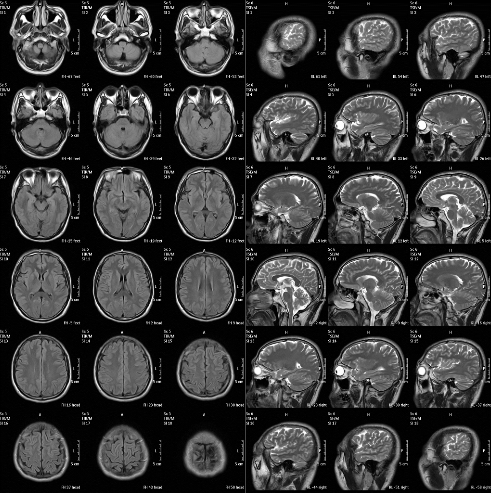

MRI(核磁)头部影像图

MRI(核磁)头部影像图是一种通过磁共振成像技术获得的头部图像,它利用磁场和射频脉冲使人体组织中的氢质子发生共振,进而产生信号,通过计算机处理这些信号生成图像。MRI头部影像图在医学诊断中具有重要地位,特别是在颅脑疾病的诊断中发挥着关键作用。